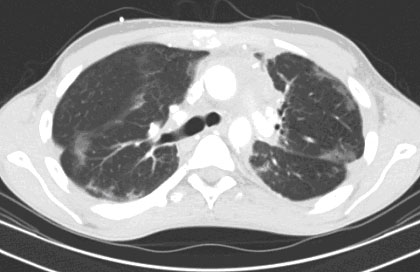

Figure 1) Computed tomography (CT) of the chest demonstrated bilateral extensive ground glass densities involving all lobes.